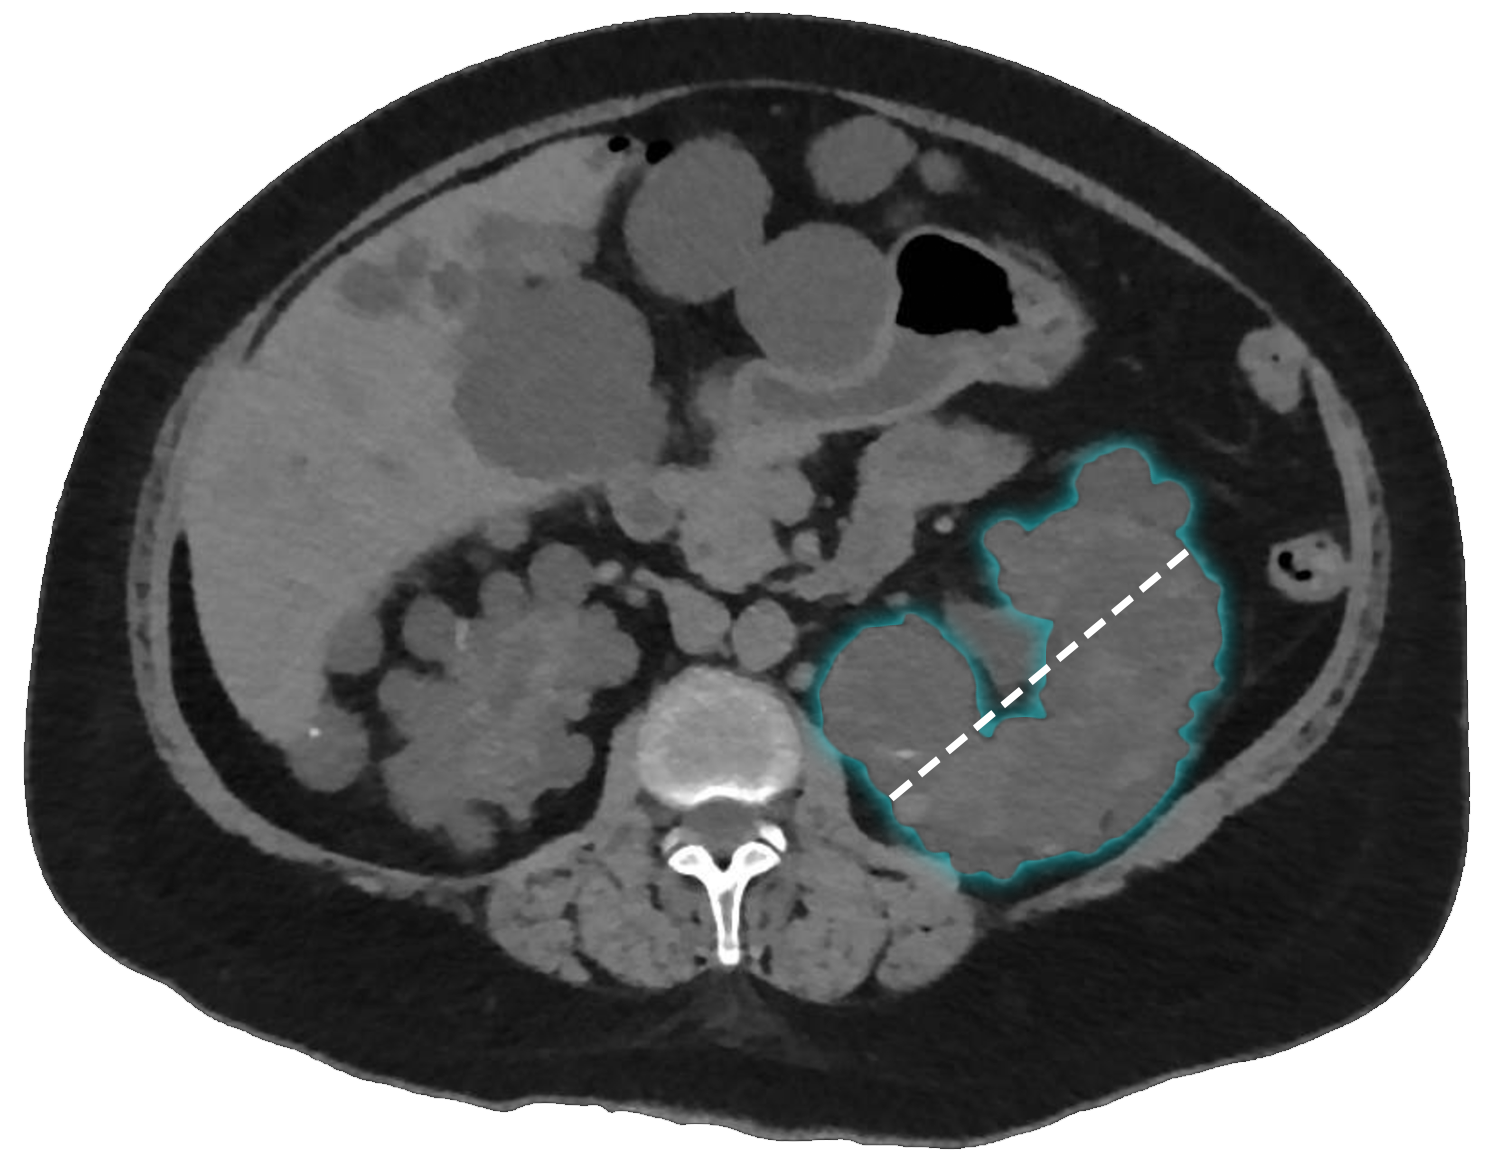

Kidney depth

Measure the depth along the axial axis using a line perpendicular to the renal hilum at the point of greatest measurement. Ensure the line traces the edge of the renal parenchyma, excluding the outline of any protruding cysts